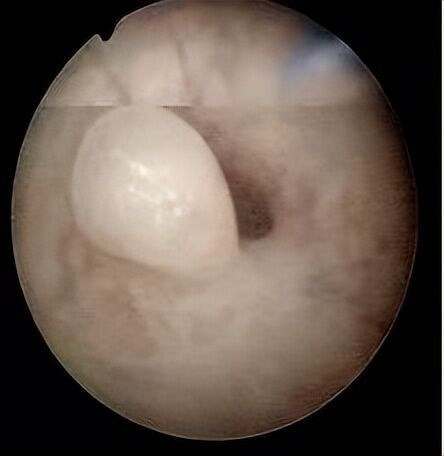

转自协和马良坤医生 相信在大家的眼中,子宫内膜就像是孕育生命的土壤,土壤是否肥沃起着关键作用,但是这片孕育之土并不是那么安宁,可存在着不少的“破坏王”,今天马姐姐就来介绍其中一个干扰性极强的“破坏王”——子宫内膜息肉。有不少的姐妹反映,做了检查发现自己有子宫内膜息肉,担心无法顺利怀孕。的确,子宫内膜息肉的发病率正在逐渐增高,对受孕也有一定的影响,那么得了子宫息肉怎么办? 息肉挡住输卵管开口